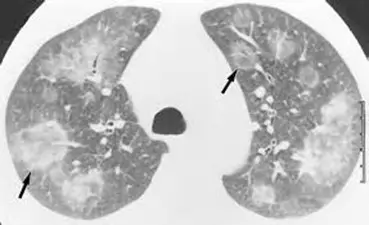

3.1.3 隐性机化性肺炎

本图为隐性机化性肺炎(cryptogenic organizing pneumonia)的特异性征象。隐性机化性肺即特发性闭塞性细支气管炎伴机化性肺炎(BOOP)。隐性机化性肺炎的影像改变有毛玻璃样变 90%、实变 87% ,反晕征 19% 但对诊断有特异性